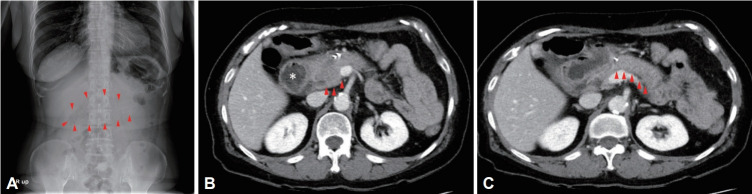

胃肠道牛黄通常是既往胃手术或胃肠道运动改变患者的并发症。胃肠道牛黄的并发症包括穿孔、腹膜炎、蛋白质丢失性肠病和急性阑尾炎。继发于十二指肠牛黄的急性胰腺炎是罕见的,很少有研究报道这种并发症。我们报告一例急性胰腺炎和随后的十二指肠梗阻引起的大十二指肠植物牛黄。

Gastrointestinal bezoars often occur as a complication of previous gastric surgery or in patients with altered gastrointestinal motility. Complications associated with gastrointestinal bezoars include perforation, peritonitis, protein-losing enteropathy, and acute appendicitis. Acute pancreatitis secondary to a duodenal bezoar is rare, and few studies have reported this complication. We report a case of acute pancreatitis and subsequent duodenal obstruction caused by a large duodenal phytobezoar.